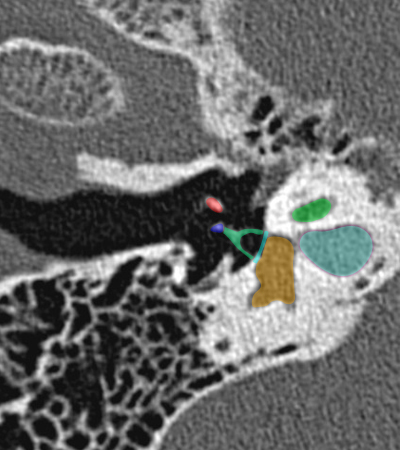

Coupe axiale passant par le canal semi-circulaire supérieur Coupe axiale passant par le canal semi-circulaire latéral Coupe axiale passant par le modiolus de la cochlée Coupe axiale passant par la fenêtre ronde Coupe axiale passant par le ganglion géniculé Coupe axiale passant par l'articulation incudo-malléaire Coupe axiale passant par la partie pétreuse de l'artère carotide interne Coupe axiale passant par le nerf tympanique